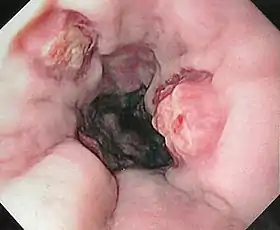

Endoscopic still of esophageal ulcers seen after banding of esophageal varices, at time of esophagogastroduodenoscopy | |

- Treatment (banding/sclerotherapy) of esophageal varices